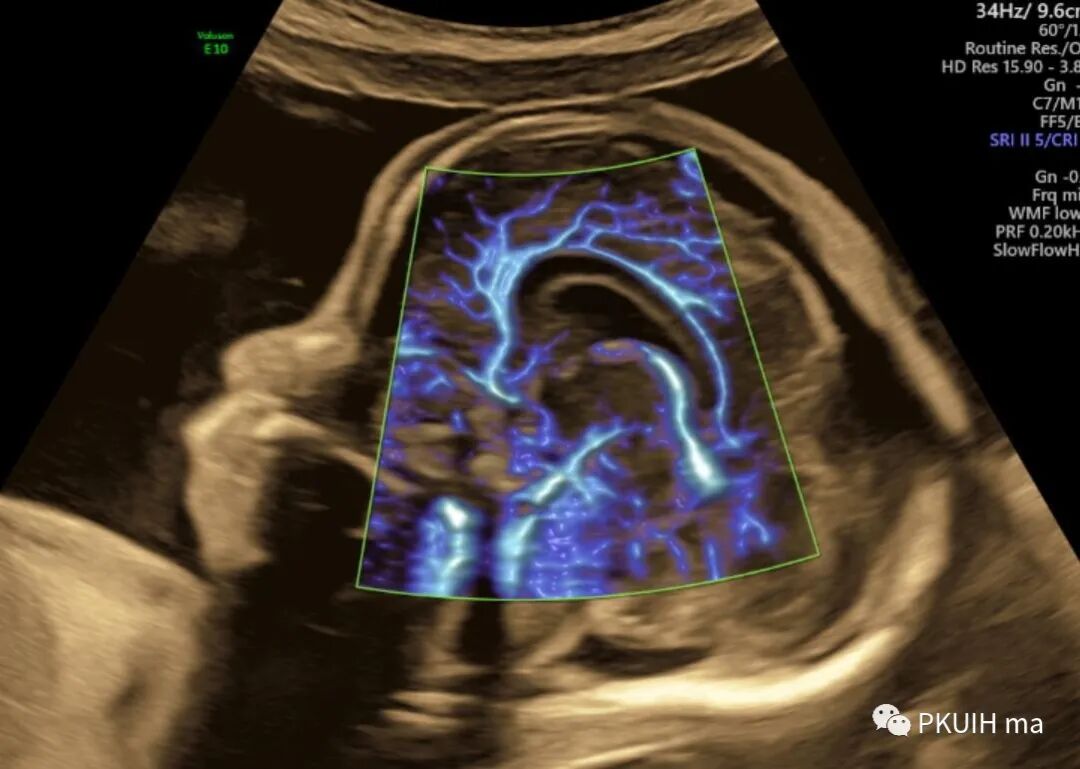

同样用这个功能我们可以很好显示胎儿胼胝体动脉及其分支,效果非常好,对于鉴别胼胝体发育有很大帮助。

另外我们可以采用各种渲染模式来显示胎儿大脑前动脉、胼周动脉及分支

另外我们也可以用此功能来显示胎儿颅内其他血管以及眼动脉和胎儿玻璃体动脉。